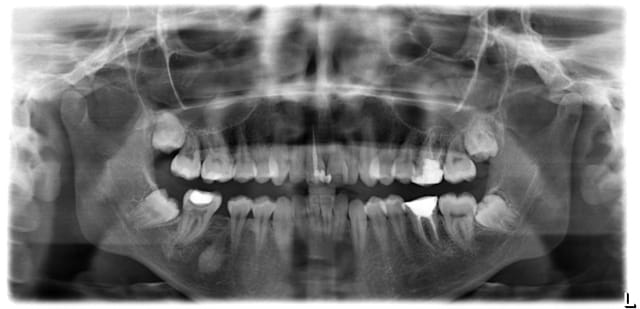

j'aurais voulu avoir vos avis concernant ce cas: il s'agit d'une femme de 23 ans qui desire ameliorer son profil et son esthetique buccal

elle presente une full classe II subdivision droite associé a la perte de la 46, une deviation importante des milieux inf vers la droite, une retrogenie associée à un contexte hyperdivergent.

c'est quoi cette image dans le secteur 4 ?

je me pose egalement la question... un artefact? je vais l'envoyer chez un dentiste pour faire une retro-alveolaire

On est coincé ici par la perte de 46 avec déviation des inférieures à droite et la pseudo classe I dentaire à gauche dans ce profil rétrognathe.